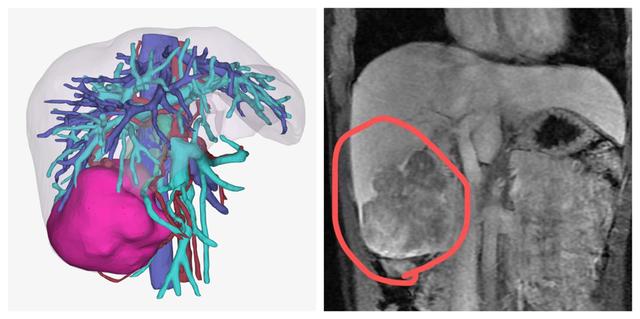

磁共振扫描结果:肝右叶巨大肿块,周围散在结节状病灶

三维重建和MRI影像图片

幸好,小黎身体状况不错,肿瘤没有侵犯临近器官,也没有远处转移,完全可以通过手术切除。经过术前检查和周密计划,医生为她做了右半肝切除手术,用时约3小时,手术顺利。术后病理确诊为肝细胞性肝癌。